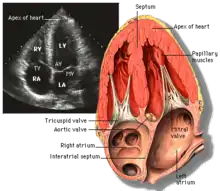

Echocardiography

Transthoracic echocardiography uses ultrasonic waves for continuous heart chamber and blood movement visualization. It is the most commonly used imaging tool for diagnosing heart problems, as it allows non-invasive visualization of the heart and the blood flow through the heart, using a technique known as Doppler.

Transesophageal echocardiography uses a specialized probe containing an ultrasound transducer at its tip is passed into the patient's esophagus. It is used in diagnosis of various thoracic defects or damage, i.e. heart and lung imaging. It has some advantages and disadvantages over thoracic or intravasular ultrasound.